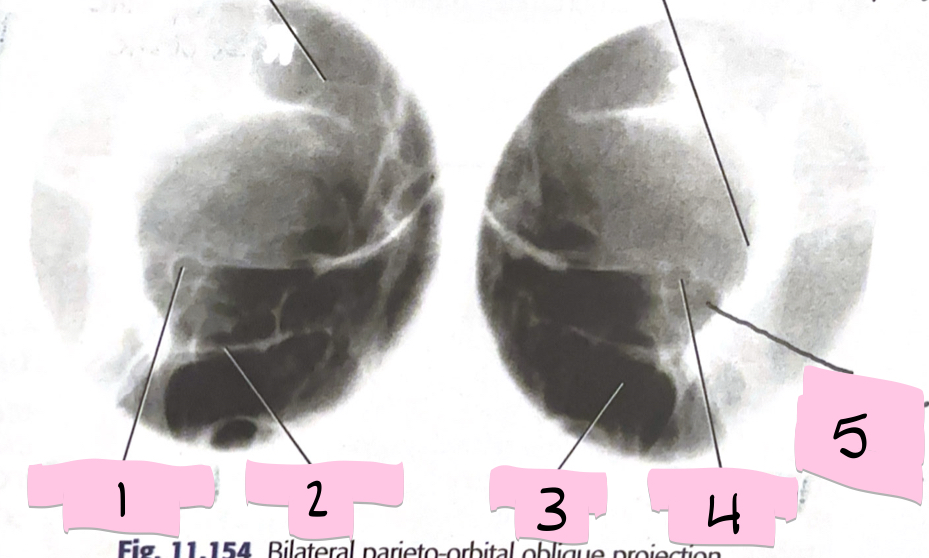

What is 1 pointing to?

Optical foramen and canal

What is 2 pointing to?

Inferior orbital rim

What is 3 pointing to?

Maxillary sinus

What is 4 pointing to?

Optic foramen and canal

What is 5 pointing to?

Superior orbital fissure